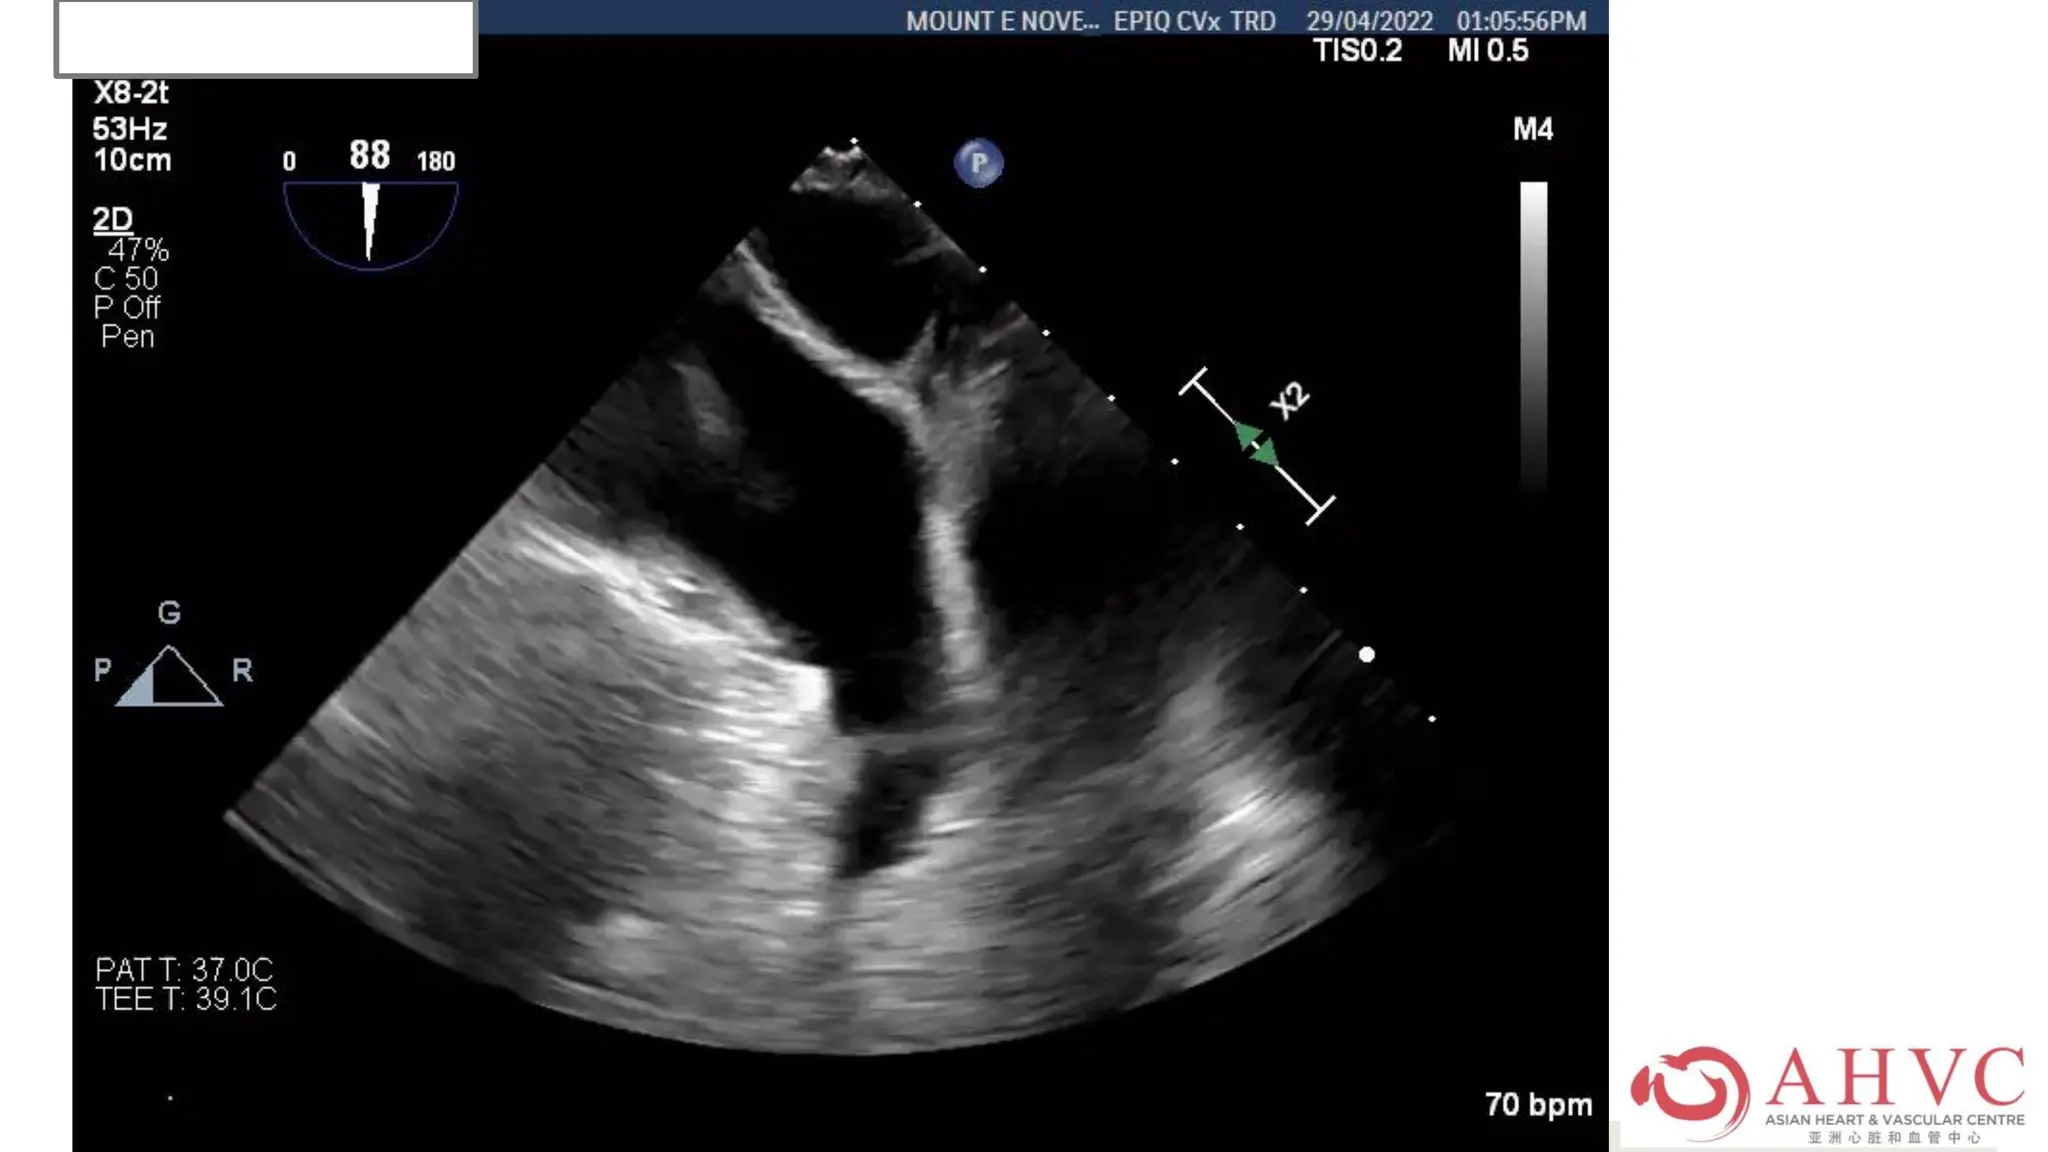

Case – Mr CKK

TEE was done before

cardioversion which showed no

clot in LAA.

His Lixiana was uninterrupted.

Case – MrCKK TEE was done before cardioversion which showed no clot in LAA. His Lixiana was uninterrupted.